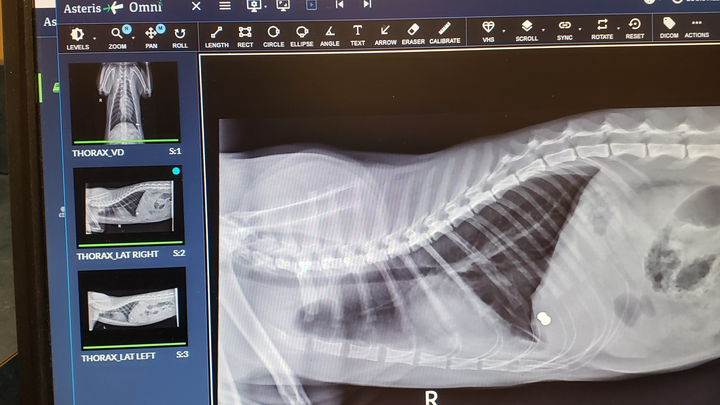

My cat came home that morning bleeding profusely from a wound on his side. When I couldn't get the bleeding to stop, I rushed him to the emergency animal hospital in Louisville. They cleaned the wound, took an x-ray, gave him a shot of antibiotics, and applied some pain medicine. $1200 later, I was informed that it appeared as tho he was targeted by someone that clearly intended to kill him (because of the type of ammunition used), but that he was "very lucky" because it missed his heart and his lungs. Which got me thinking: I have another cat that went missing on November 2nd, which is highly unlike her to not come home; what are the odds that something unrelated happened to both of my cats only a few weeks apart? I feel that it is highly unlikely for that to be the case. What I think happened, is that my other cat wasn't so "lucky", which breaks my heart to think about. Why would someone target my cats with the intention to kill them?! If they were bothering you somehow, why not come talk to me about it? Whatever happened to being "neighborly"?